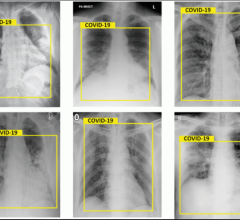

This photo gallery shows the variety of radiological presentations of COVID-19 (SARS-CoV-2) in medical imaging, including computed tomography (CT) ...